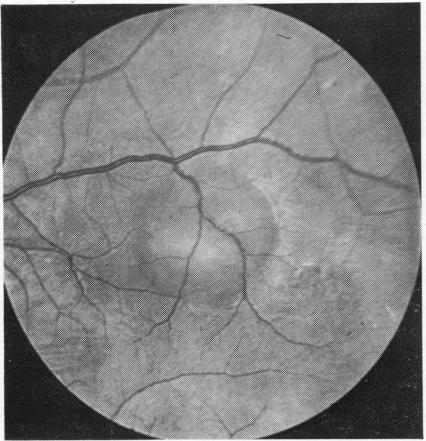

Periarteritis nodosa and thrombotic thrombocytopenic purpura in siblings is reported. In both patients a localised serous retinal detachment and lesions of the retinal pigment epithelium had developed owing to choroidal vascular obstruction. These cases support the suggested possible relationship between the two conditions.

据报道,同胞兄妹患结节性多动脉炎和血栓性血小板减少性紫癜。两名患者均因脉络膜血管阻塞出现局限性浆液性视网膜脱离和视网膜色素上皮病变。这些病例支持了这两种疾病之间可能存在关联的观点。